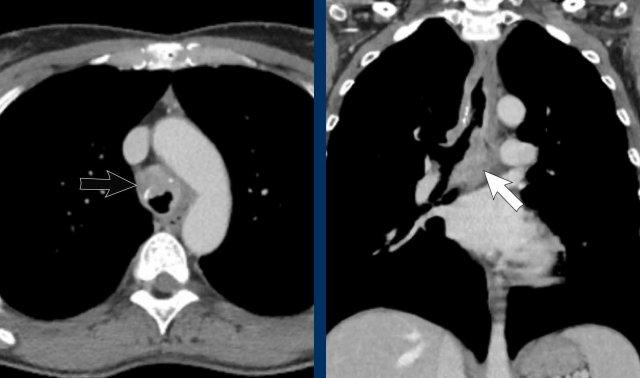

Hình ảnh

Viêm trung thất xơ hóa bên phải ở nam giới 51 tuổi, cho thấy tổn thương tỷ trọng mô mềm xung quanh phế quản chính phải (mũi tên).

Cùng bệnh nhân.

Có các dấu hiệu thứ phát của chèn ép đường thở trung tâm và mạch máu, với mất thể tích phổi khu trú và dày mô kẽ do phù nề.